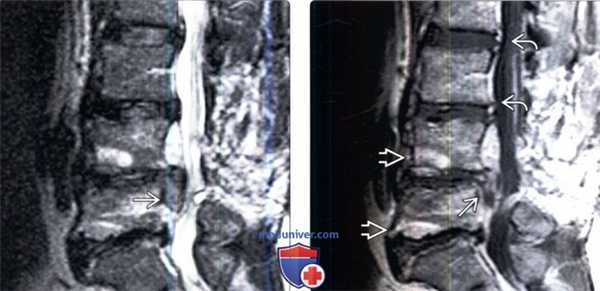

(Слева) Сагиттальный срез, Т2-ВИ: крупная рецидивная грыжа диска L5-S1. Видны признаки дегенерации этого диска в виде снижения его высоты и снижения интенсивности Т2-сигнала.

(Справа) На аксиальном Т1-ВИ определяются гомогенные изменения мягких тканей вдоль вентральной и левой боковой поверхности дурального мешка с минимальной деформацией последнего — это типичная картина перидурального фиброза.

(Слева) Сагиттальный срез, Т2-ВИ: крупная рецидивная грыжа диска L4-L5, деформирующая дуральный мешок и мигрирующая вниз до уровня L5 позвонка. Видны признаки выраженных дегенеративных изменений L3-4, L4-L5 и L5-S1 сегментов.

(Справа) На сагиттальном Т1 -ВИ с КУ не накапливающая контраст рецидивная грыжа окружена накапливающей контраст зоной фиброза на уровне L4-L5. Также видны признаки многоуровневого дегенеративного поражения позвоночника, дегенеративные изменения замыкательных пластинок II типа ЕЯ и расслоение фиброзных колец межпозвонковых дисков.